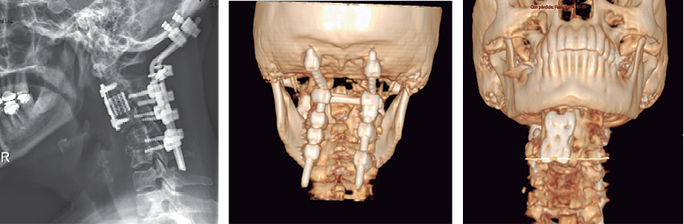

El día 27 de Noviembre se llevó a cabo el primer procedimiento quirúrgico con laminectomía de C1 y C2, instrumentación posterior occipitocervical, con colocación de barras y tornillos transfacetarios bilaterales desde C3-C6 hasta crosslink. Se egresó por mejoría el 29 de Noviembre con estado neurológico Frankel D por parestesias en manos con FM 5/5, sensibilidad conservada y reflejos osteotendinosos ++/++. Se volvió a intervenir el día 29 de Enero de 2014 con abordaje transoral con disección de tejidos blandos, realizando corpectomía de C3, colocación de malla intersomática y placa anterior fijada con tornillos; sin presentar complicaciones en el transoperatorio ni en el postoperatorio, fue egresada el 31 de Enero (Figuras 3). Finalmente la paciente acudió a valoración a radioterapia para radioablación en lesiones hepáticas y oncología médica para concluir sesiones y ser egresada para control de tumor primario.

Figuras 3 a 5: Estudio radiográfico simple y tomográfico de reconstrucción. 9 de Febrero de 2014. Resultado postoperatorio con instrumentación anterior (malla intersomática y placa anterior) y posterior (barras occipitocervical con fijación con tornillos y crosslink).